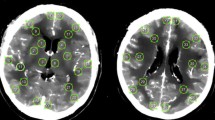

Complete T1-weighted data was obtained for 27 patients (Fig. 1), while diffusion-weighted data was obtained in 14 patients due to constraints on length of time in the scanner for some patients.

Assessment 1: < 72 h post-SAH

SIENA-X analysis showed significant apparent higher total brain volume, whole-brain GM and WM volumes in patients compared with healthy controls, while ventricular CSF volumes showed a trend towards higher values in patients (Table 2, Fig. 2A). In line with the apparent higher whole-brain GM volume, we found a significantly lower mean GM ADC values for the patients compared with controls (Table 2, Fig. 2A).

Voxel-by-voxel regional analysis using VBM showed that this apparent higher GM volume in the patients was widespread, particularly in regions including the anterior cingulate/paracingulate gyrus, primary motor cortex, left supramarginal and angular gyrus, fusiform gyrus (especially on the right), basal ganglia (caudate and putamen bilaterally) and cerebellum (Fig. 2A).